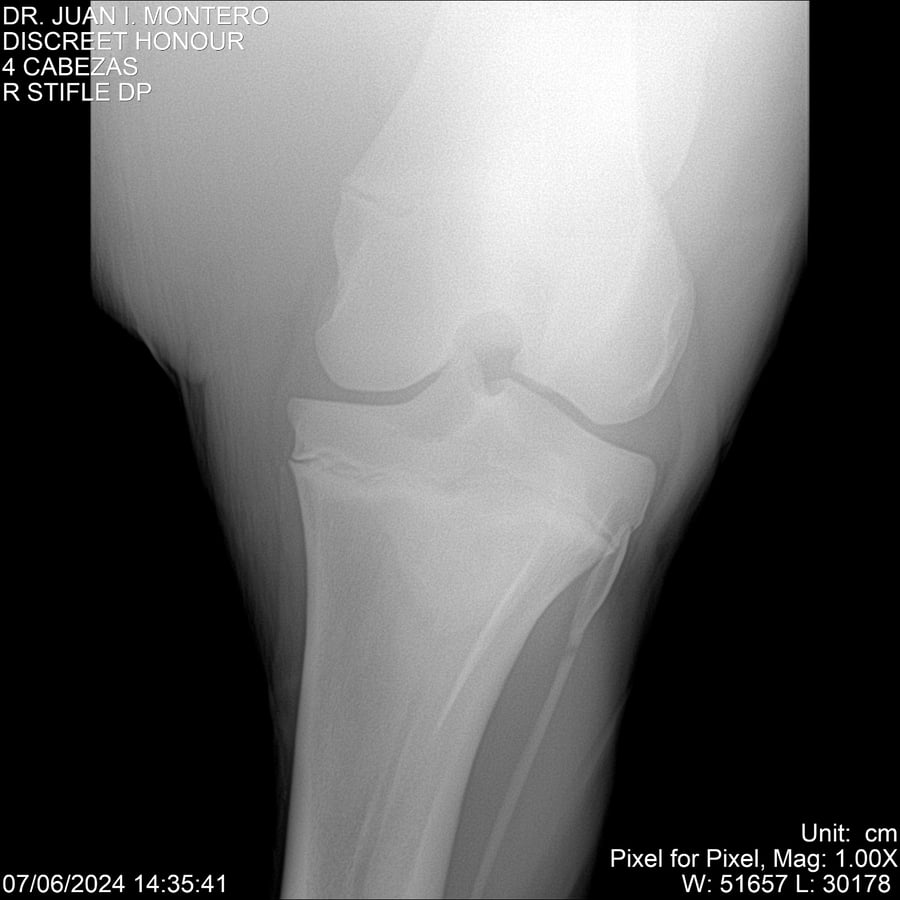

LOTE 6, DISCREET HONOUR 🔥 🔥 🔥 Lote Anterior Volver al remate Lote Siguiente Ficha Contacto Montevideo - Ficha del Lote Identificador: #281093 Categoría: Yeguarizos Montevideo - 82 Visualizaciones ClicData Contacto Empresa: Abelenda N. R., Walter Hugo Nombre*: Teléfono* : E-mail* : Mensaje Enviar Registrese gratis Este contenido Exclusivo está disponible sólo para usuarios registrados Ingresar